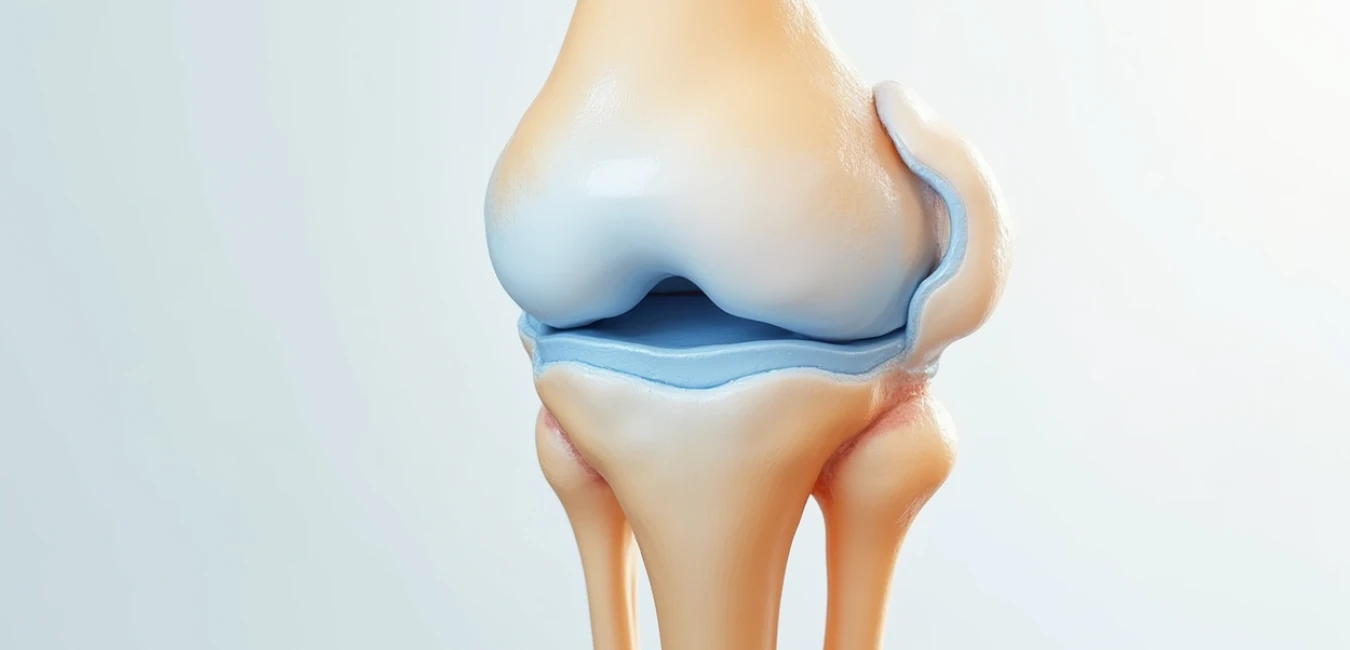

Staw to ruchome połączenie między końcami kości, składające się z powierzchni stawowych pokrytych chrząstką szklistą. Ta gładka i elastyczna tkanka amortyzuje wstrząsy, zmniejsza tarcie i umożliwia płynny ruch. Torebka stawowa, mocna i włóknista, otacza staw i stabilizuje go, a wewnątrz znajduje się jama stawowa wypełniona mazią stawową, która smaruje powierzchnie i chroni przed ścieraniem. Błona maziowa produkuje tę maź, a więzadła wzmacniają strukturę, ograniczając ruchy do bezpiecznego zakresu. W organizmie występuje ponad 300 stawów, różniących się budową i funkcją – od prostych połączeń międzypaliczkowych po złożone stawy nadgarstka czy stopy.

Układ ruchu funkcjonuje dzięki harmonijnej współpracy kości, stawów, chrząstek, więzadeł i mazi stawowej. Kości pełnią rolę dźwigni mechanicznych, a stawy umożliwiają różnorodne ruchy w zależności od budowy. Stawy jednoosiowe, jak zawiasowe między paliczkami, pozwalają na zginanie i prostowanie w jednej płaszczyźnie. Stawy dwuosiowe, np. siodełkowaty w podstawie kciuka, umożliwiają ruchy w dwóch kierunkach. Największą swobodę zapewniają stawy wieloosiowe kuliste – staw barkowy oferuje szeroki zakres ruchu dla ramienia, podczas gdy biodrowy łączy mobilność ze stabilnością niezbędną do przenoszenia ciężaru ciała.

Stawy wykazują zmienną podatność na kontuzje w zależności od budowy. Staw barkowy, wieloosiowy i płytki, oferuje szeroki zakres ruchu, ale jest bardziej narażony na zwichnięcia. Kolano jako staw złożony podlega dużym obciążeniom podczas chodzenia i biegania. Stopa z 26 kościami i 33 stawami zapewnia stabilność i amortyzację, ale łuki podłużny i poprzeczny wymagają prawidłowego wsparcia mięśniowo-więzadłowego, by zapobiec płaskostopiu czy problemom z chodzeniem. Degradacja chrząstki, zaburzenia produkcji mazi stawowej czy niedobory składników budulcowych kości to typowe wyzwania wymagające odpowiedniego wsparcia żywieniowego.